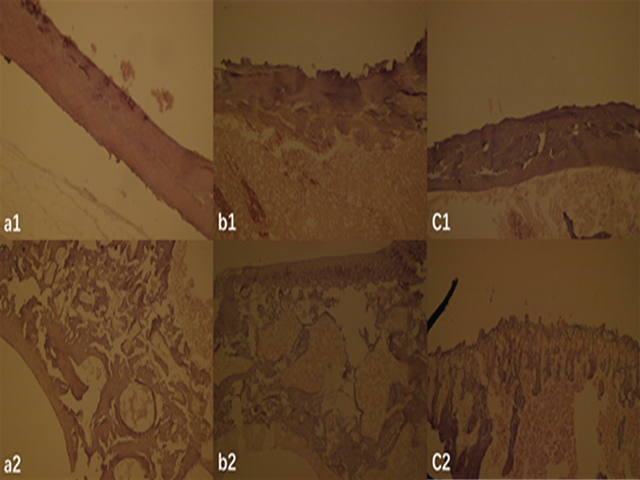

Spectrum–Effect Relationships between Fingerprints of Radix Polygoni multiflori‑Achyranthes bidentate and Antiosteoporosis Effect Based on Different Extraction Solvents